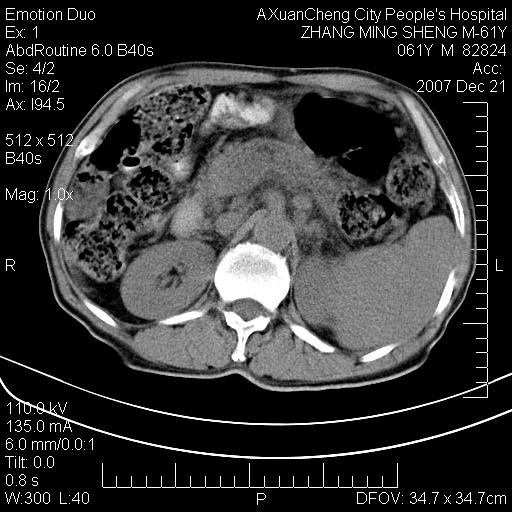

标题: CT11031:M61Y,胰腺占位 [打印本页]

标题: CT11031:M61Y,胰腺占位

大家侃侃门静脉和胆管系统怎么回事,肝内转移?

胰腺癌肝转移

肝硬化,门脉高压,脾肿大;弥漫性肝癌,肝内、门脉、腹膜后淋巴结转移,肝内外胆管扩张,胰头区占位,建议mr检查

胰腺癌伴肝内转移;门脉、肠系膜上v癌栓形成。

考虑为:胰腺癌伴肝脏转移、腹膜后淋巴结转移,门静脉及肠系膜上静脉瘤栓形成。

胰体尾癌伴肝内转移,门静脉及肠系膜上静脉瘤栓形成.

肝硬化,脾大. 胰腺癌伴肝内转移;门脉、肠系膜上v癌栓形成。